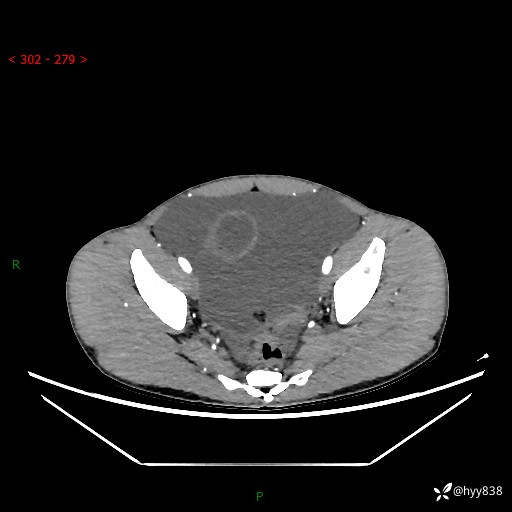

现病史:患者10天前无明显诱因出现腹部胀痛不适,无畏寒发热,无胸痛胸闷,无心慌气短,无恶心呕吐,无腹泻及黑便,无粘液血便及里急后重等症状,4天前在当地县人民医院就诊,行腹部CT示:下腹部占位性病变,腹腔及盆腔积液;今患者为求进一步诊治来我院治疗,门诊以“腹水”收治入院。 发病以来,精神饮食可,大小便正常,体重体力无明显变化。

腹部CT平扫+增强